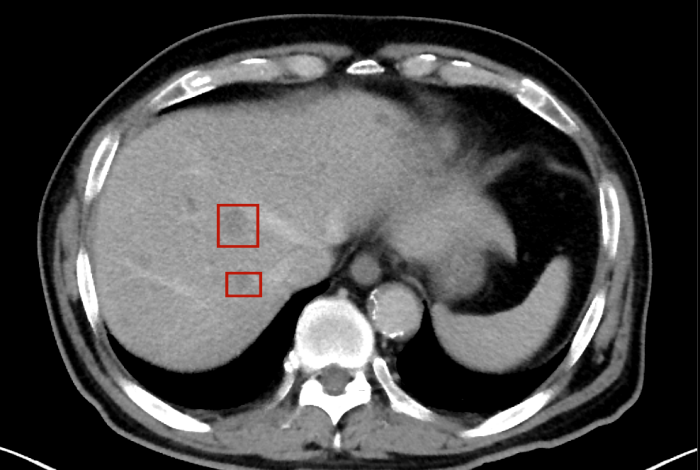

術(shù)后,萬秀萍為黃先生做進一步的檢查,腹部磁共振(MRI)檢查顯示:肝臟區(qū)域出現(xiàn)了轉(zhuǎn)移病灶的陰影。

轉(zhuǎn)移病灶的陰影